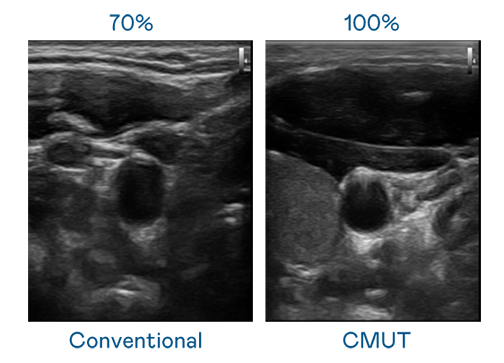

CMUT 技术是一种用电容式微机电元件来产生超音波讯号的技术。与传统 PZT 压电式技术相比,CMUT 频宽增加 30%,更宽频的超音波讯号让影像解析度大幅提升,是实现高影像品质医疗超音波扫描、促进精准医疗发展的关键技术。

超音波影像的解析度高低,首先取决于探头能发出的讯号频宽。Bodog CMUT 可提供高清晰的超音波讯号,提供高频宽、高灵敏度、影像纹理细节更高的超音波影像,协助医护人员缩短影像判读时间及利用精准的医疗影像进行诊断。